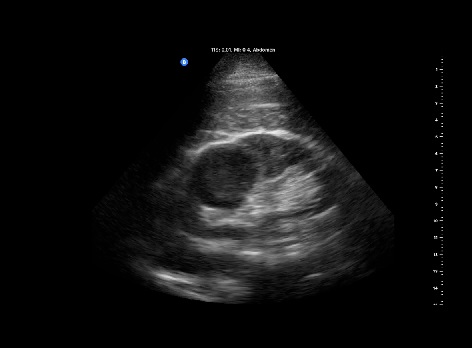

Se realiza con sonda ecográfica portátil. Se inicia el estudio ecográfico del abdomen a nivel de la línea axilar media derecha, donde realizamos cortes longitudinales y transversales. En el riñón derecho se observa, a nivel del polo superior, una lesión sólida heteroecoica, hipoecogénica respecto al parénquima circundante, redondeada, de bordes bien definidos, sin refuerzo posterior (figura 1), de 4,10 x 4,56 cm (figura 2) y con vascularización (Doppler positivo) (figura 3).